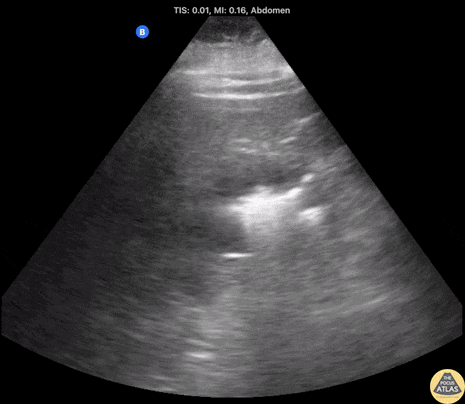

60 year old female with poorly controlled diabetes. Initial CT showing R-sided pyelonephritis, US performed 12 hours later demonstrated development of emphysematous pyelonephritis noted by the hyperechoic areas with dirty shadowing seen within the renal parenchyma (indicative of gas). This was later confirmed on repeat CT imaging. Contributor: Shane Solger, MD Kings County/SUNY Downstate EM/IM